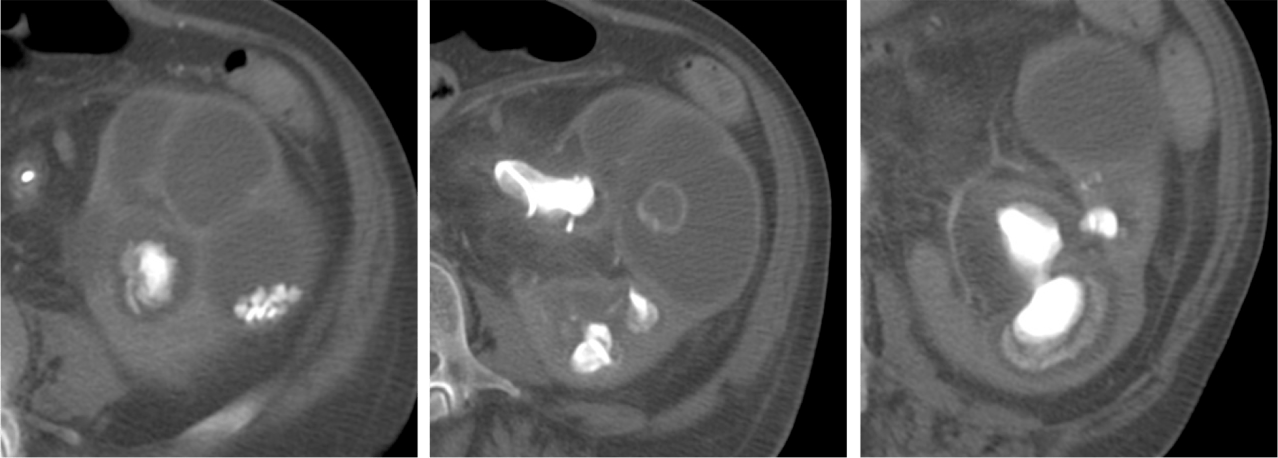

Veamos un caso.

Paciente mujer de 62 años que acude por decaimiento general con fiebre y dolor en flanco izquierdo. Ingresa en UVI por signos de sepsis

Nos cuenta antecedentes de pielonefritis e hidronefrosis crónica.

Hallazgos en imagen:

Estos hallazgos pueden ser dificiles de interpretar, ya que una paciente con hidronefrosis crónica y litiasis en el uréter puede haber sufrido una obstrucción que origina un cuadro de dolor en FRI con ruptura de cálices y colección extra axial. Otra probabilidad puede ser un angiomiolipoma que ha roto un aneurisma y ha producido un sangrado. También podríamos estar ante una pionefrosis aunque dada dada la clínica, los antecedentes y al observar los hallazgos en TC podríamos establecer la sospecha de pielonefritis xantunogranulomatosa con alta probabilidad. La confrimación vendrá dada con la nefrostomía y estudio de anatomía patológica.